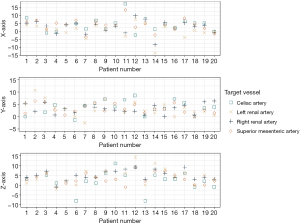

The displacement of the four target vessels showed a poor correlation to each other, meaning that the vessels all moved in different directions and to different extents. The intraclass correlation was 0.37 (0.18–0.58), 0.16 (0.00–0.38) and 0.56 (0.38–0.74) in terms of x-, y- and z-axis displacement, respectively. This non-uniformity of the target vessel movement is further visualized in Figure 5.